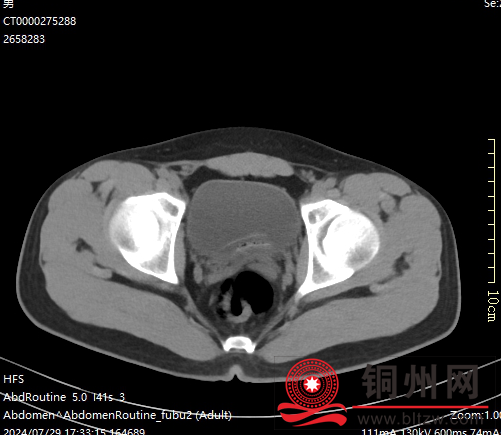

上图:入院CT检查考虑膀胱异物(黄鳝)

精准诊断:多学科协作明确病情